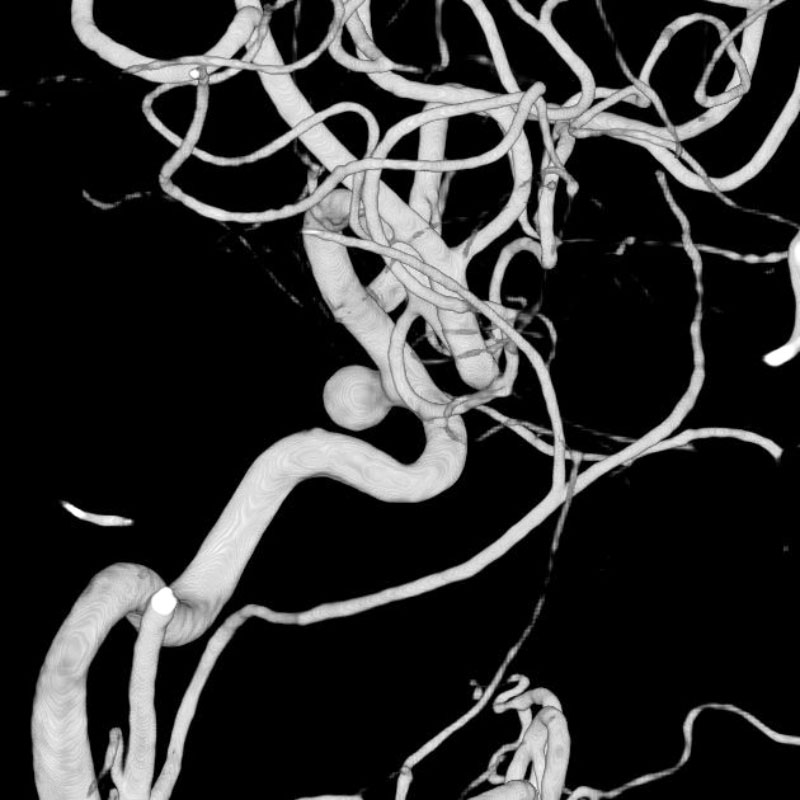

左頚部内頚動脈狭窄症

経皮的頸動脈ステント留置術

須山/松田/濵田